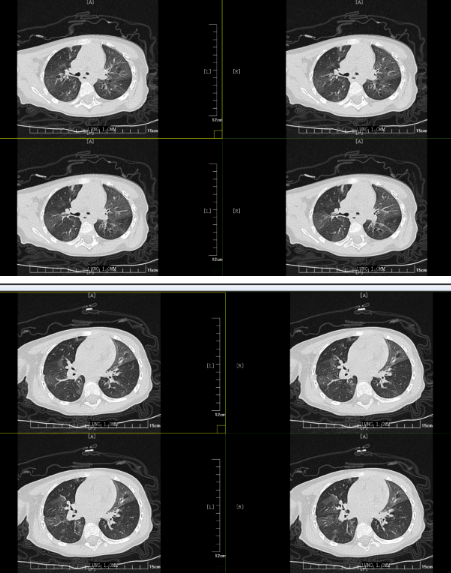

但胸部CT的結(jié)果表明小丸子的肺內(nèi)病變比較重,同時(shí)通氣也不均勻,確實(shí)存在堵塞,可這個(gè)"堵住氣管的東西”到底是什么,還得在支氣管鏡檢查下才能知道。在和小丸子的父母詳細(xì)溝通病情后,入院第二天一早,小兒內(nèi)科田恬主任便為其進(jìn)行了無痛電子支氣管鏡檢查。